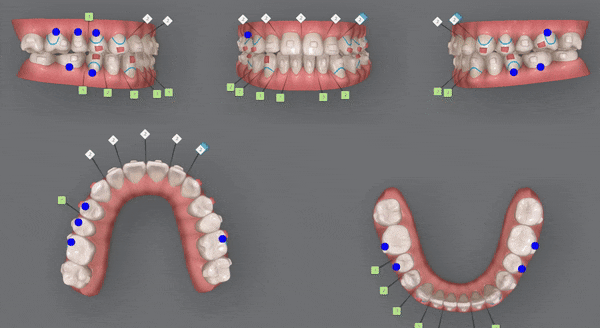

인비절라인의 장점 중의 하나는

교정 후의 모습을 예측할 수 있는것 입니다.

원장님께서 클린체크 디자인을 마치게 되면

인비절라인 교정치료 후에

치아이동이 어떻게 변화하는지 클린체크를 통해 확인 해 볼 수 있는것인데요.

클린체크대로

치아들이 움직이면서 점점 가지런해 지는게 보이시나요?

첫번째 클린체크에서는 잠실교정치과 유펜바른치과에서 총 46개의 장치로

진행 해드렸습니다.

악궁이 점점 확장되면서 삐뚤빼뚤했던 치열들이 가지런하게 배열되고,

윗니 아랫니 사이의 공간이 점점 닫히며,

반대교합이 개선되면서 정상적인 교합으로

변하고 있는 모습을 확인해 보실 수 있습니다 ^^